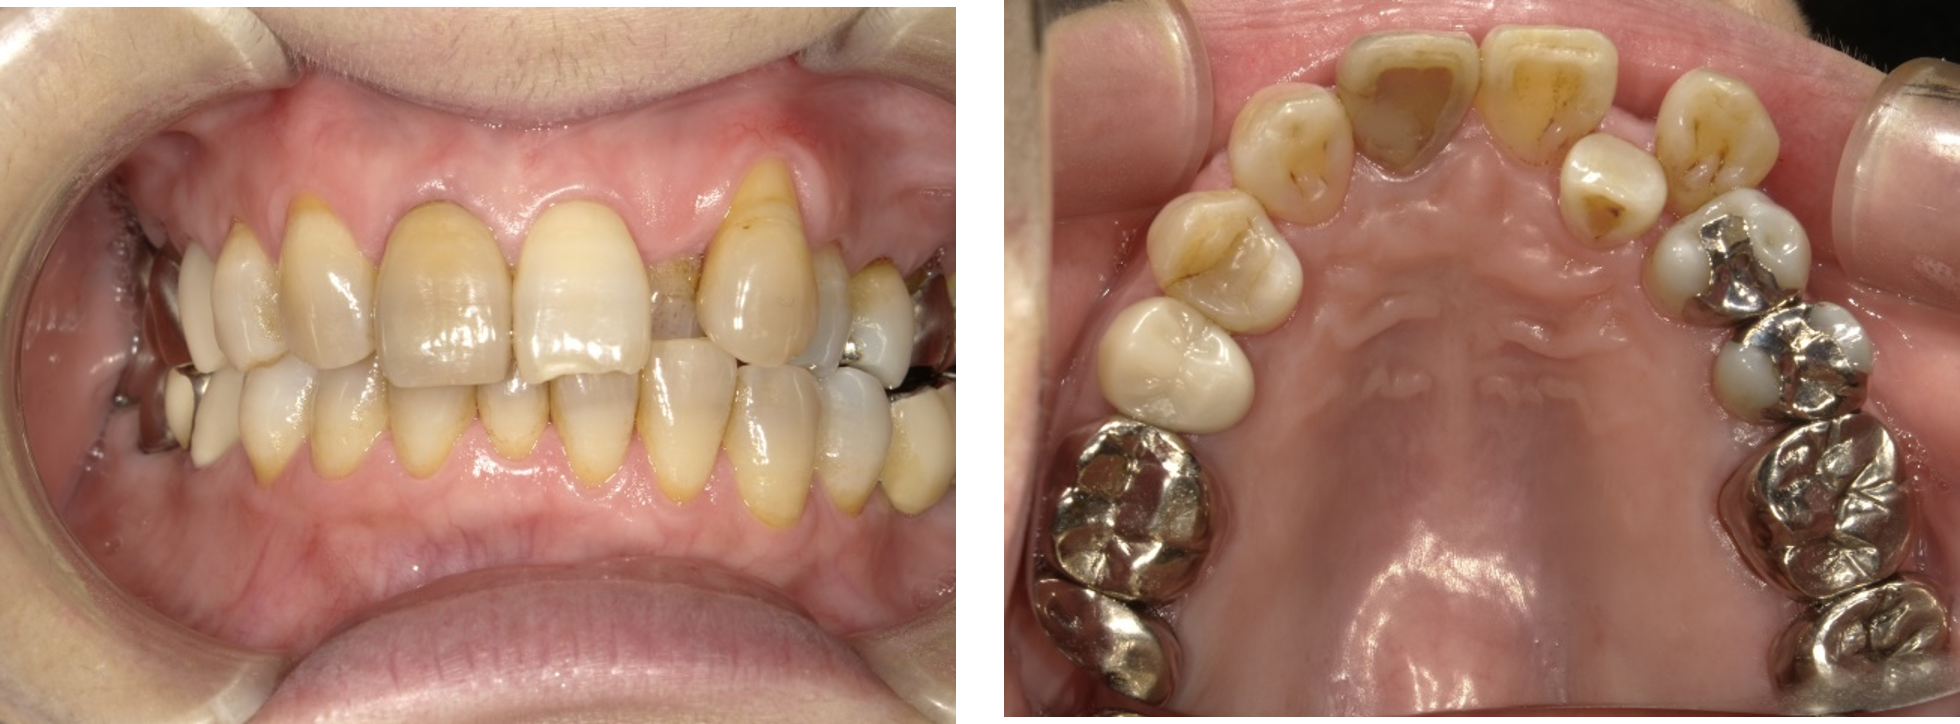

上の図のような悪い歯並びは、多くの場合、全顎矯正(全部を矯正する)で対応することが多いですが、臨床的には、気になる部分を少し矯正する(部分矯正)だけで対応できるケースも多くあります。

実際に当院で部分矯正治療を受けられた方の感想です。